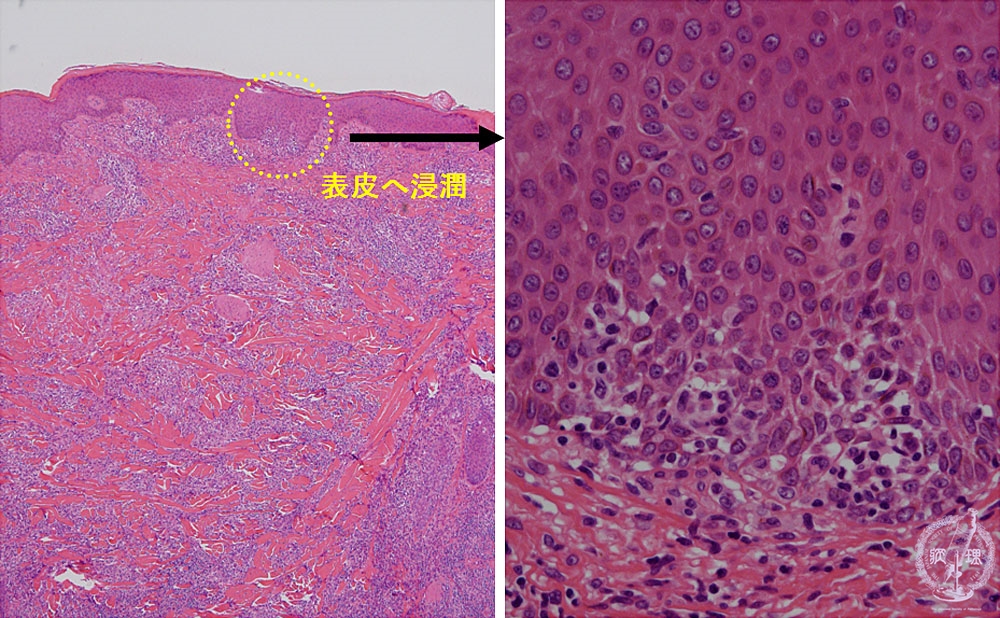

- (11)Malignant lymphoma of the skin (Mycosis fungoides)

Microscopic findings: In advanced stage (tumor stage), lymphoma cells are diffusely seen in the dermis with epidermotropism (inside the circle).